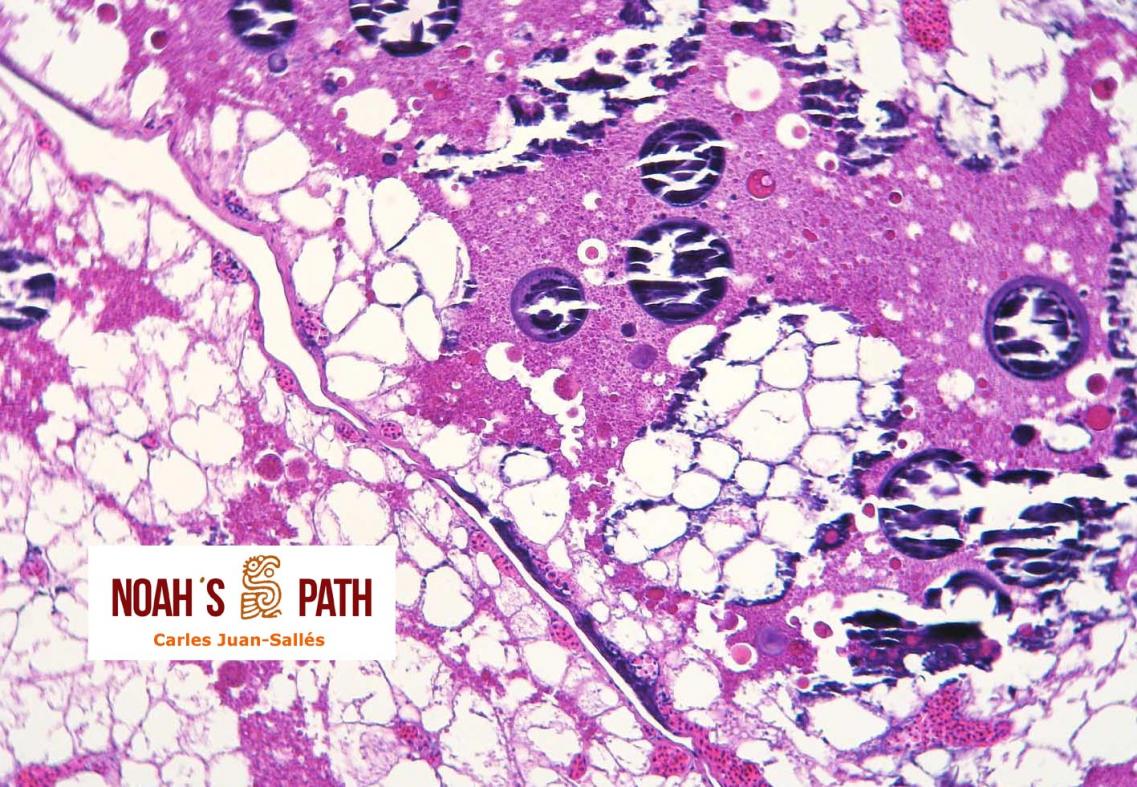

Ara ararauna

Mineralización de saco vitelino